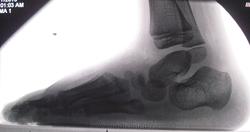

Прошу у вас помощи в диагностике косолапости. И ещё, имеет ли место остеохондропатия ладьевидной кости (келер 1) левой стопы? С косолапостью никогда дело не имел, к сожалению. И подходящей литературы нет.

Для оценки оперированной косолапости важно описать положение таранной кости и состояние таранно-пяточного сустава, т.к вправление тарана - один из необходимых моментов в лечении. Также необходимо оценить степень остаточного приведения переднего отдела стопы, т.е. состояние суставов Лисфранка и Шопара.

Келер маловероятен, скорее имеет место дегенеративные изменения в ладьевидной кости вследствие выполненных оперативных вмешательств а также других факторов.

Приводящая деформация обеих стоп.

Здесь приводящая деформация стоп. Справа в меньшей степени, чем слева.